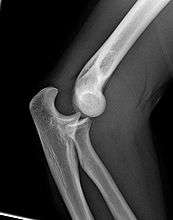

Right: AP X ray of a dislocated right elbow

The types of disease most commonly seen at the elbow are due to injury.

Fractures

There are three bones at the elbow joint, and any combination of these bones may be involved in a fracture of the elbow. Patients who are able to fully extend their arm at the elbow are unlikely to have a fracture (98% certainty) and an X-ray is not required as long as an olecranon fracture is ruled out.[22] Acute fractures may not be easily visible on X-ray.

Dislocation

Elbow dislocations constitute 10% to 25% of all injuries to the elbow. The elbow is one of the most commonly dislocated joints in the body, with an average annual incidence of acute dislocation of 6 per 100,000 persons.[23] Among injuries to the upper extremity, dislocation of the elbow is second only to a dislocated shoulder. A full dislocation of the elbow will require expert medical attention to re-align, and recovery can take approximately 8–14 weeks. A small amount of people (10% or less) report near full recovery and minimal permanent restriction, but a permanent restriction of 5–15% movement is common.